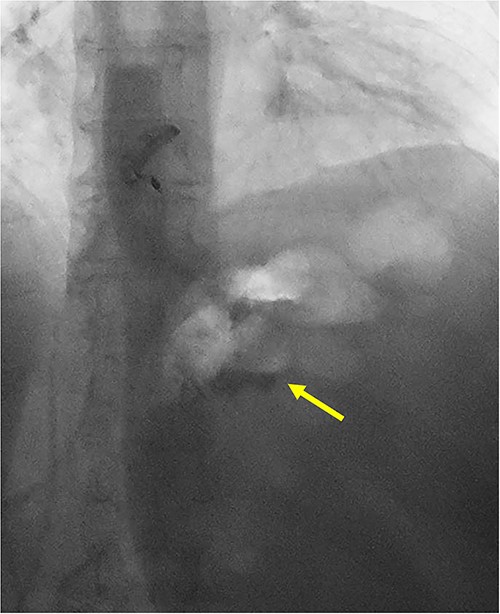

She underwent a CT of her abdomen and pelvis that showed concern for a possible gastrogastric fistula (Fig. 1) that was confirmed via an upper GI series demonstrating the passage of oral contrast into the remnant stomach (Fig. 2). Subsequent esophagogastroduodenoscopy (EGD) also revealed an ulcer at the site of the GGF (Fig. 3). The patient was discharged home on Omeprazole twice daily. She was seen in the outpatient setting with bariatric surgery and scheduled in 3 months for laparoscopic take-down of her gastrogastric fistula.

Cross-sectional CT imaging demonstrating concern for gastrogastric fistula.

UGI series demonstrating passage of oral contrast from gastric pouch to remnant stomach.